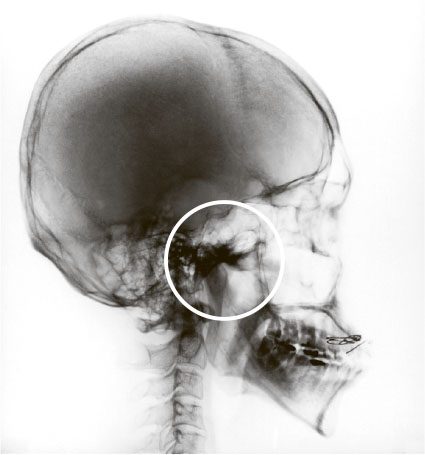

РЕНТГЕНОГРАФИЯ ЧЕРЕПА В БОКОВОЙ ПРОЕКЦИИ

В последнее время стало модным оценивать таким способом гипертрофию аденоидов у детей. Да, она покажет условный размер носоглоточной миндалины (в виде расплывчатого пятна), но при этом никакой информации о расположении аденоидной ткани относительно других структур полости носа и носоглотки мы не получаем. А это основополагающая информация для оценки вреда, причиняемого дитятке.

Аденоиды в кружочке. Как мы видим, кроме условного размера (который часто ни на что не влияет) ничегошеньки понять нельзя